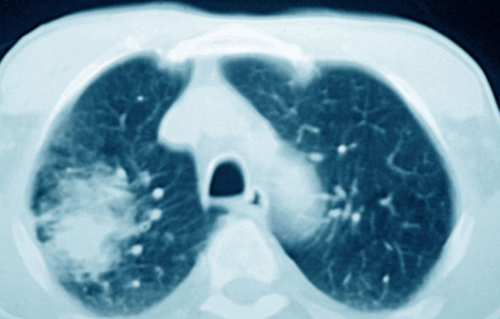

肺部有阴影是什么原因,肺部有阴影CT

肺部有阴影CT

肺部阴影诊断

肺部阴影有几种可能

新冠肺部阴影

肺部ct

正常肺部ct图

肺部恶性肿瘤ct图片

正常肺部ct片

正常肺部ct高清图